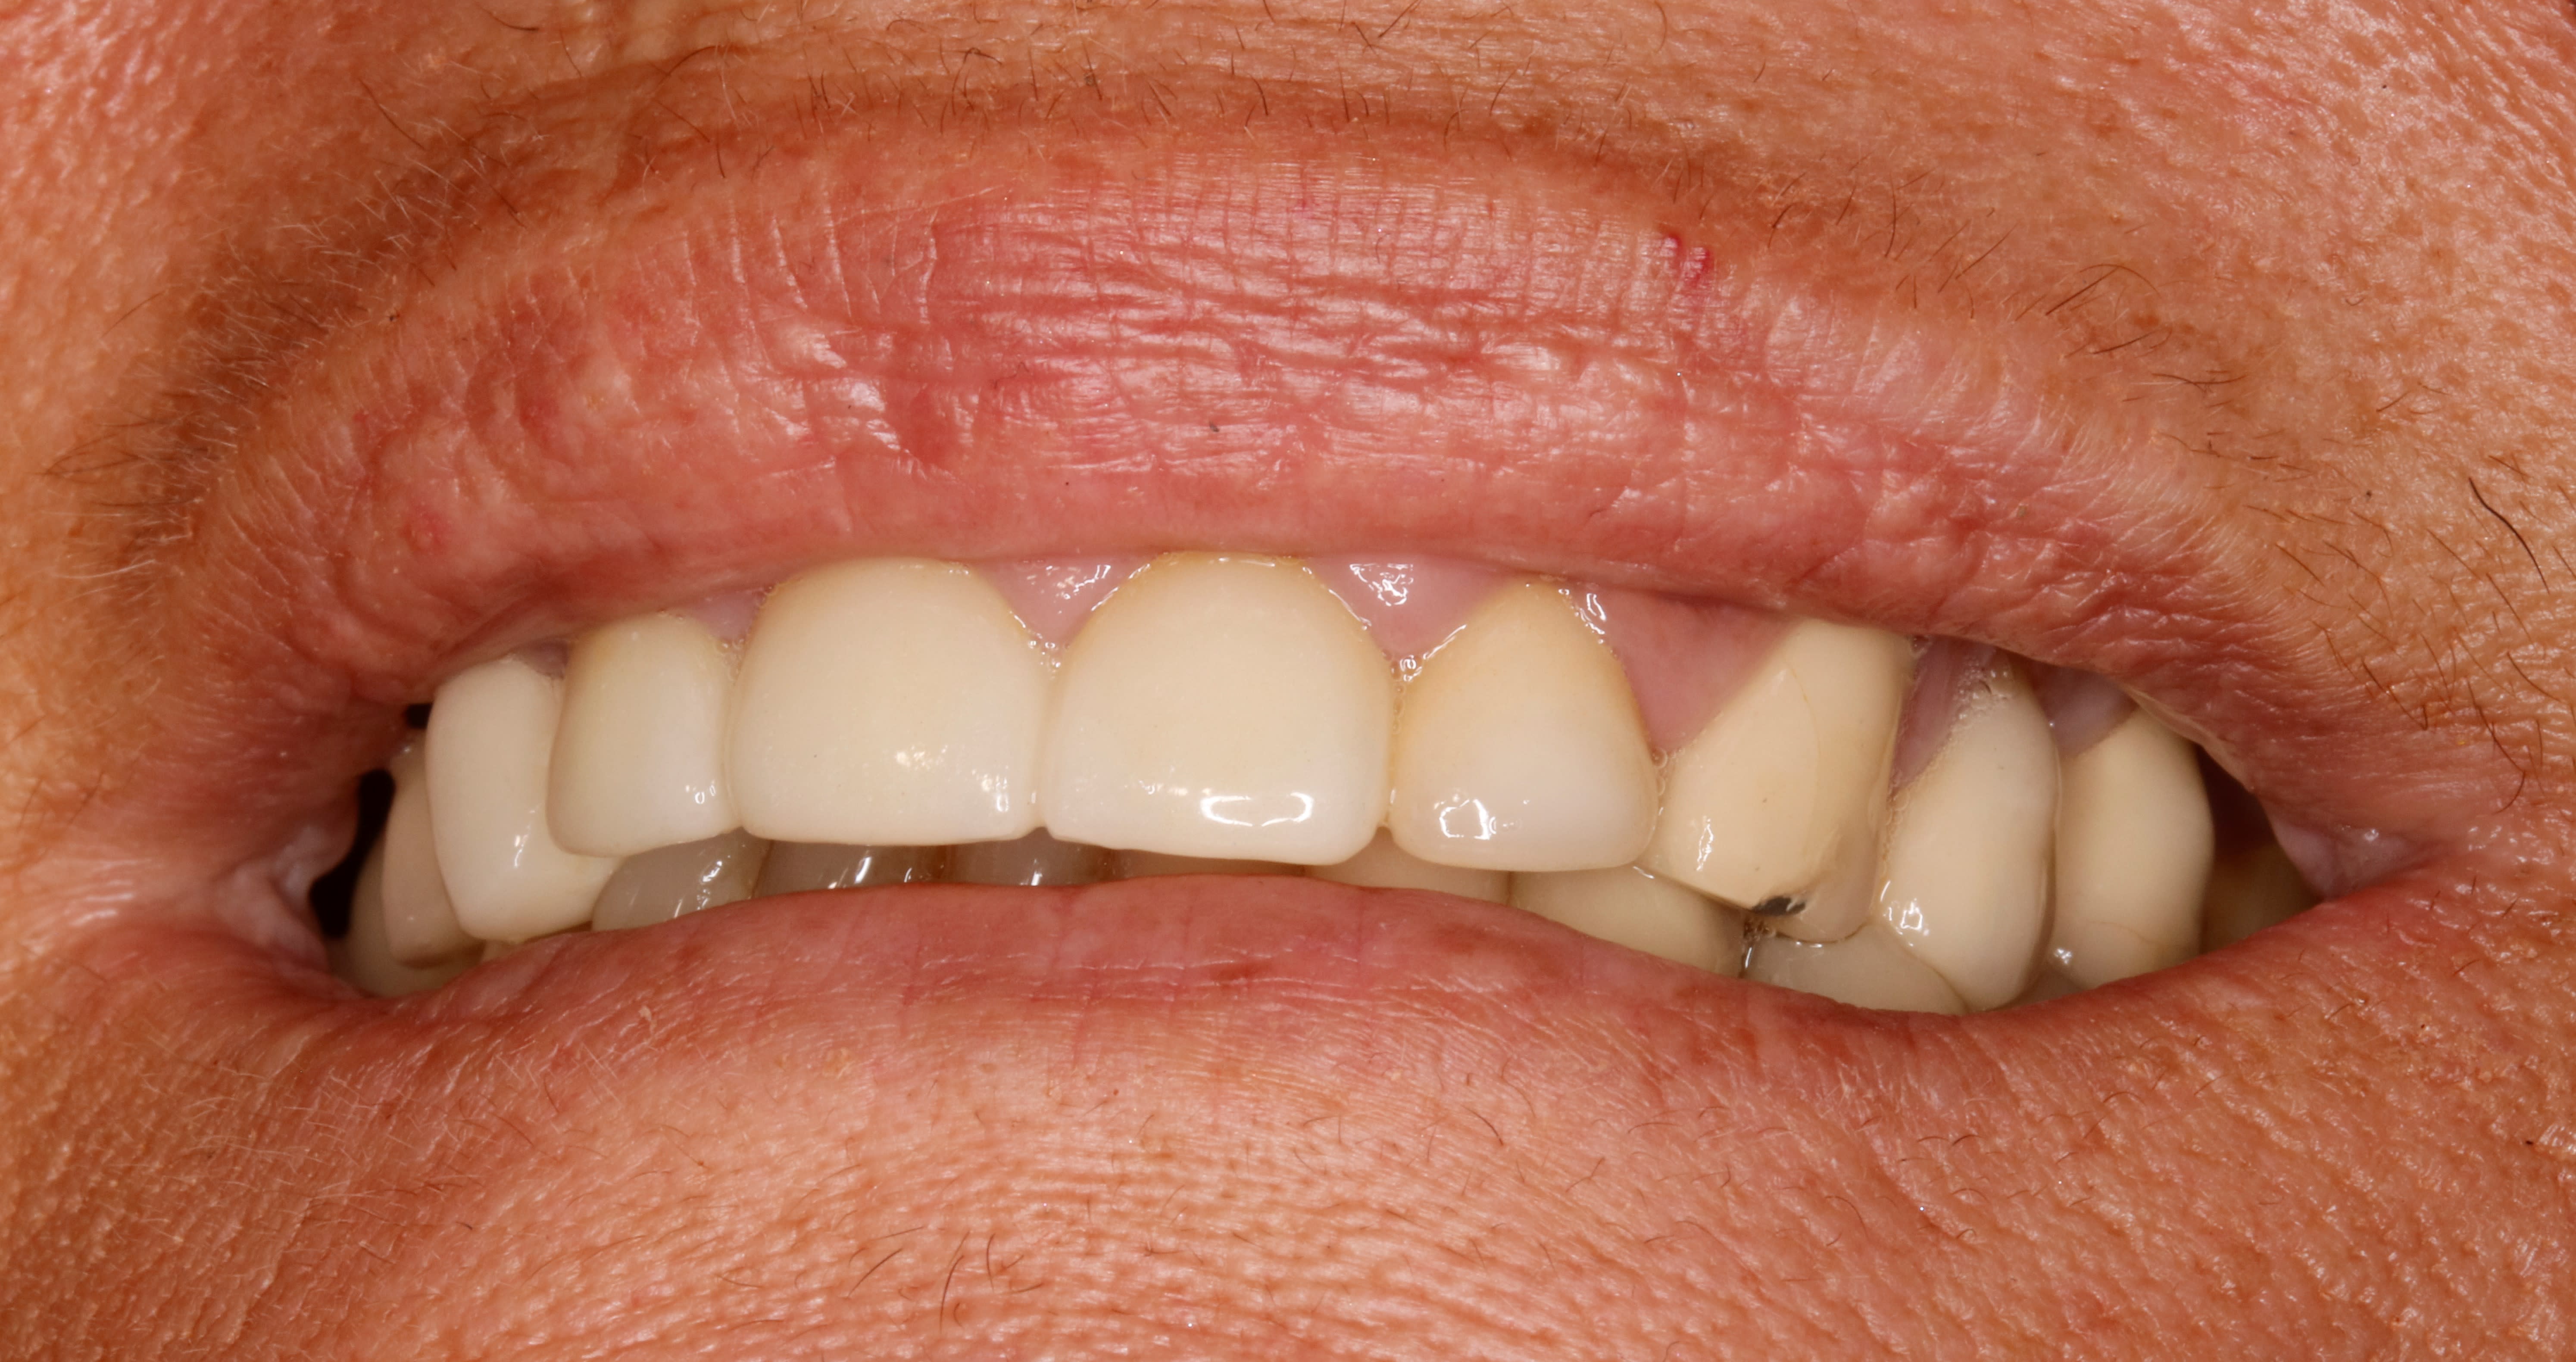

les coulegues , voilà un petit quizz rapidos pour jouer à 3000 e le point :-)

une belle inconnue arrive en urgence entre 2 pour resceller sa 14 implantaire .

manifestement , il doit certainement y avoir un pb occlusal , et t as juste 2s pour trouver où ca !

quel dent ai je limé ???

un indice : il en a eu 2 plus exactement , 1 plus une autre après mais faut pas se tromper dans l ordre .